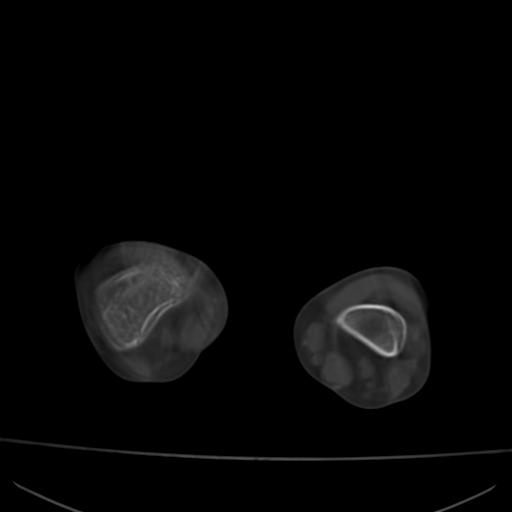

标题: PED0940:M12Y,左股骨下端酸痛畸形 [打印本页]

标题: PED0940:M12Y,左股骨下端酸痛畸形

12岁男孩,左膝关节肿痛8年,近月明显

内生骨软骨瘤?

血友性关节病?